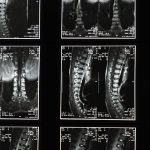

La décompression neurovertébrale est une méthode efficace pour traiter les déséquilibres musculo-squelettiques liés à des tensions nerveuses chroniques, notamment dans la région du cou. En exerçant une traction contrôlée sur la colonne vertébrale, cette technique crée un espace entre les vertèbres, ce qui réduit la pression sur les nerfs spinaux. Cela permet de soulager les douleurs cervicales et favorise une amélioration de la circulation sanguine, tout en libérant les tensions musculaires. En ciblant spécifiquement les zones de compression, la décompression neurovertébrale aide ainsi à restaurer l’équilibre et le confort du patient.

La décompression neurovertébrale utilise un appareil spécialisé pour exercer une traction contrôlée sur la colonne vertébrale. Cette traction crée un espace entre les vertèbres, réduisant ainsi la pression sur les nerfs spinal. En créant un effet de vide, cette technique favorise le repositionnement et la guérison des disques intervertébraux, permettant ainsi un meilleur flux sanguin et une réduction des inflammations. Pour en savoir plus sur le fonctionnement de cette méthode, consultez ce lien.

La décompression neurovertébrale fonctionne en appliquant une traction contrôlée sur la colonne vertébrale. Cette traction crée un espace entre les vertèbres, permettant ainsi de diminuer la pression qui pèse sur les nerfs. En ciblant spécifiquement le cou, la technique aide à relâcher la tension nerveuse et à rétablir l’équilibre musculo-squelettique.

Comment cette méthode agit-elle sur les maux de cou? La décompression neurovertébrale crée un espace entre les vertèbres cervicales, ce qui réduit la compression exercée sur les structures nerveuses et favorise la circulation des fluides dans la colonne vertébrale. Cette traction contrôlée permet de relâcher les tensions accumulées, facilitant ainsi la récupération des tissus environnants. En agissant directement sur la source de la douleur, cette technique contribue à diminuer l’inflammation et à soulager les symptômes associés aux pathologies cervicales.